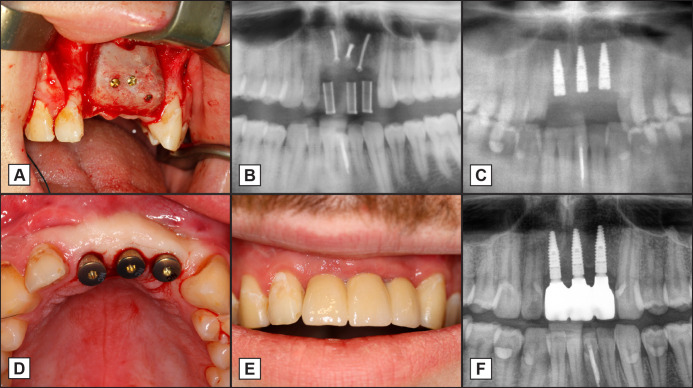

Objectives: This prospective follow-up study aimed to evaluate the stability values of tapered titanium implants inserted into maxilla following ridge augmentation with free iliac bone graft and crestal bone changes up to three years of follow-up.

Material and methods: A total of seven patients with 34 tapered titanium implants in the maxilla with fixed protheses were enrolled in this prospective follow-up study. Patients with previously augmented maxillae using free iliac bone grafts were included. Implant stability was measured (Osstell™) for up to three months of healing. Peri-implant bone resorption was measured using radiographic images taken immediately after implant surgery and after three years. Using a clinical and radiological examination survival and success rates were evaluated.

Results: After implant insertion, the stability was 60.93, whereas the stability increased significantly (P = 0.0192) to 64.97 at implant exposure (after 3 months). The mean bone loss around the implants was 1.13 mm after three years. Clinical parameters revealed a mean sulcus depth of 2.76 (1.18) mm and a bleeding on probing score of 0.29 (0.58). The survival rate was 100%, and the success rate was 67.65% at the end of the study.

Conclusions: Tapered implants can be used in free iliac bone grafts for fixed dentures. Implant stability values were high after insertion. In terms of a success rate of 67.65%, the patient's jaw reconstruction indicated a reduced implant success when comparing the data with healthy patients without any augmentation procedures.